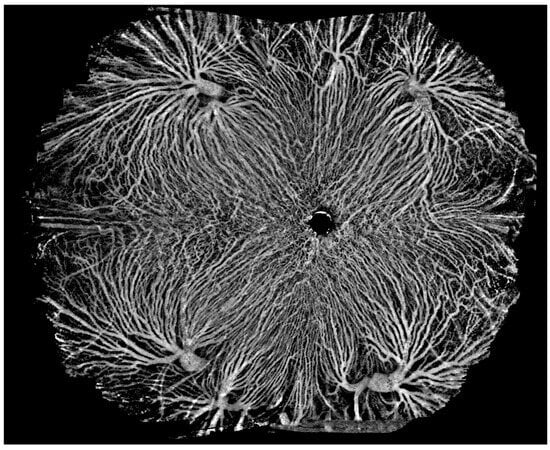

The core device in SS-OCT is a frequency-swept laser source, which emits coherent, narrow-band light. It has the advantages of single-point scanning, characteristic of TD-OCT, and fast imaging, characteristic of SD-OCT, which are integral for en face OCT and OCT angiography (OCTA). SS-OCT also has an improved speed of data acquisition and computerized data-processing capabilities. At present, commercial SS-OCT offers speeds of 100,000, 200,000, and 400,000 sweeps per second. In 2019, Intalight launched the first device in ophthalmic SS-OCT capable of 200,000 sweeps per second (SVision VG200, SVision Imaging, Ltd., Luoyang, China) to obtain China National Medical Products Administration clearance. Carl Zeiss established an ophthalmic SS-OCT device capable of 200,000 sweeps per second (Elite 9000, Carl Zeiss AG, Oberkochen, Germany) in the EU and US five months later. In 2020, TowardPi unveiled their ophthalmic SS-OCT system, capable of 400,000 A-scans per second (BM-400K BMizar, TowardPi Medical Technology Ltd., Beijing, China), and started marketing it in China one year later. SS-OCTA provides wider and finer scans than SD-OCTA, and even though its range is several times wider than that of SD-OCTA, local details remain clear when the image is enlarged. Figure 1 is an example of a healthy eye examined via high-resolution, widefield SS-OCTA with a speed of 200,000 sweeps per second and a range of 12 × 12 mm (1024 × 1024 pixels). The central area displays copasetic detail of macular capillaries, which is barely possible with SD-OCTA.

Figure 1.

A healthy eye examined via high-resolution, widefield swept-source (SS) optical coherence tomography angiography (OCTA), with a range of 12 × 12 mm. The central area displays copasetic detail of macular capillaries.